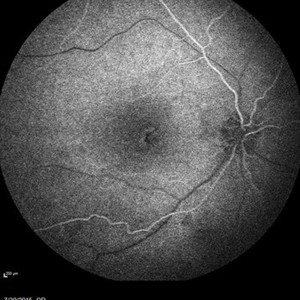

Retinal Dystrophy of 24-Year-Old Male Early FA OD

Nov 25 2015 by Zach Dupureur

Fluorescein angiography of a 24-year-old male. Juvenile retinoschisis on OCT. FA shows outer retinal staining. Could be associated with Goldmann Farve Syndrome.

Condition/keywords: Goldmann-Favre Syndrome, juvenile retinoschisis, retinal dystrophy